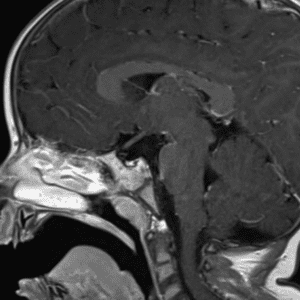

Case #11

Medulloblastoma